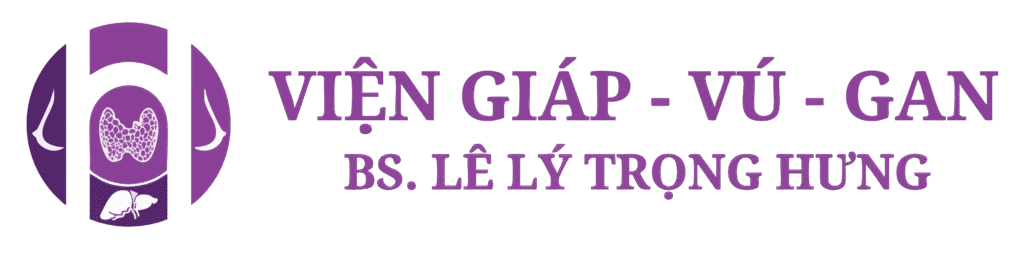

- Kết quả siêu âm:

- Núm vú trái to hơn phải, mất cấu trúc lớp và có hình ảnh tăng sinh mạch máu so với núm vú phải

- Ngay sau núm vú trái có cấu trúc echo kém, giới hạn không rõ, bờ gai, không vôi hoá, phân bố mạch máu ngoại vi, kt# 11x9mm ( BIRADS 4B)